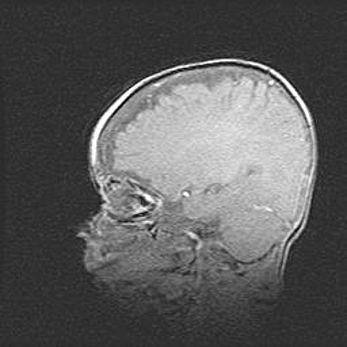

Сообщающаяся гидроцефалия. Кистозная энцефаломаляция головного мозга.

Возраст: 3 месяца 4 дня

Вес: 3100 г

Пол: женский

Окружность головы: 34 см

Срок гестации: 31 неделя

Кистозная энцефаломаляция головного мозга - одна из форм поражения головного мозга в детском возрасте. Характеризуется возникновением множественных и распространённых кист в коре, белом веществе и подкорковых образованиях головного мозга у плодов, новорождённых и детей раннего возраста. Развитие кистозной энцефаломаляции связано с внутриутробной асфиксией и гипотонией, родовой травмой, тромбозом синусов, пороками развития сосудов, инфекциями, сепсисом и другими причинами. Наиболее значимые инфекционные агенты: вирусы простого герпеса, цитомегалии, краснухи, токсоплазмы, энтеробактерии, золотистый стафилококк и другие.